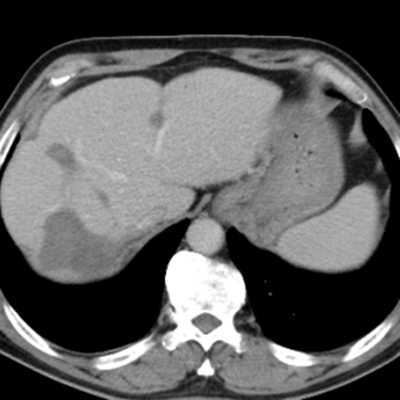

組織腸癌MDT診療團隊進行病情討論,診斷為腸癌伴肝、肺、腹腔、縱膈轉(zhuǎn)移,其中肝轉(zhuǎn)移瘤數(shù)目在50枚以上,最大的約10cm,并伴有腸梗阻,情況不容樂觀。

隨后,根據(jù)基因檢測結(jié)果制定了化療+靶向治療方案。經(jīng)過精準(zhǔn)治療,劉大爺?shù)牟≡畲笮⊙杆倏s小,病灶數(shù)量不斷減少,影像學(xué)評估已經(jīng)看不見之前那些小的病灶了。

治療前:箭頭處均為轉(zhuǎn)移性腫瘤

治療后:未見明顯活性轉(zhuǎn)移腫瘤

經(jīng)過兩次肝臟轉(zhuǎn)移瘤射頻消融手術(shù),一次腸癌根治手術(shù)聯(lián)合腹腔轉(zhuǎn)移腫瘤切除手術(shù),劉大爺體內(nèi)的大腫瘤完全消除,僅有幾處沒有明確活性的小病灶。